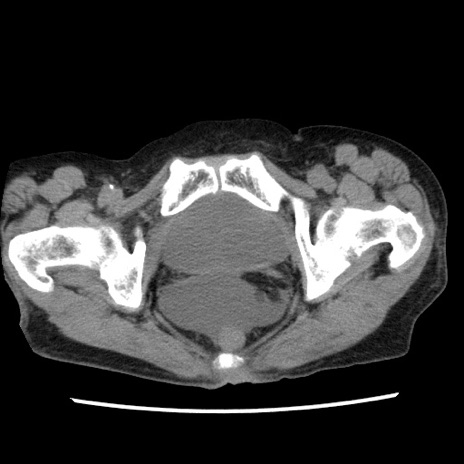

矢状断像

【症例】80歳代女性

【主訴】腹痛

【現病歴】8時間前から腹痛あり来院。

【既往歴】糖尿病、脂質異常症、子宮体癌にて子宮全摘術

【身体所見】意識清明・会話良好だが腹痛で苦悶様、全腹部にわたって反跳痛と圧痛あり

【データ】WBC 13600、CRP 0.14、LDH 224、CK 90